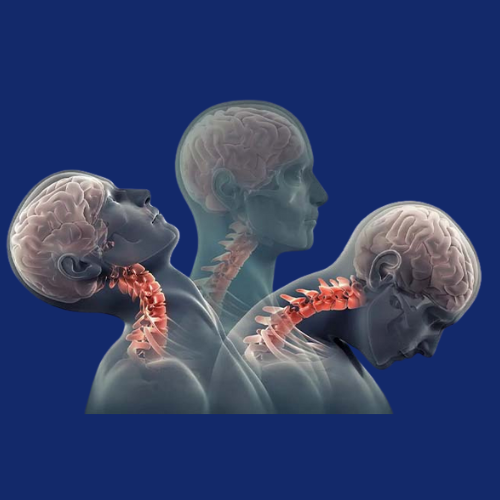

The cervical spine, located in the neck region, plays a crucial role in supporting the head and enabling motion. However, it is also prone...Read More

The cranio-vertebral junction (CVJ) is a complex anatomical region at the junction of the skull and upper cervical spine (C1–C2), responsible for supporting...Read More